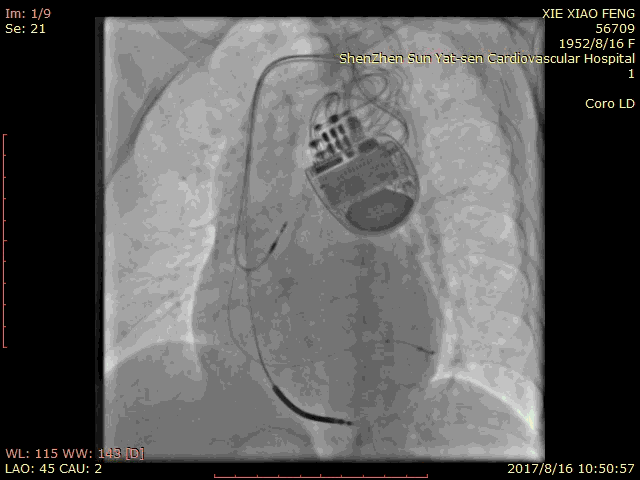

血管选择 一

血管选择二

血管选择三

术中测试

● 左心室阈值:LV4-Coil 1.25V

● 右心室阈值:0.5V

● 右心房阈值:0.5V

最终影像